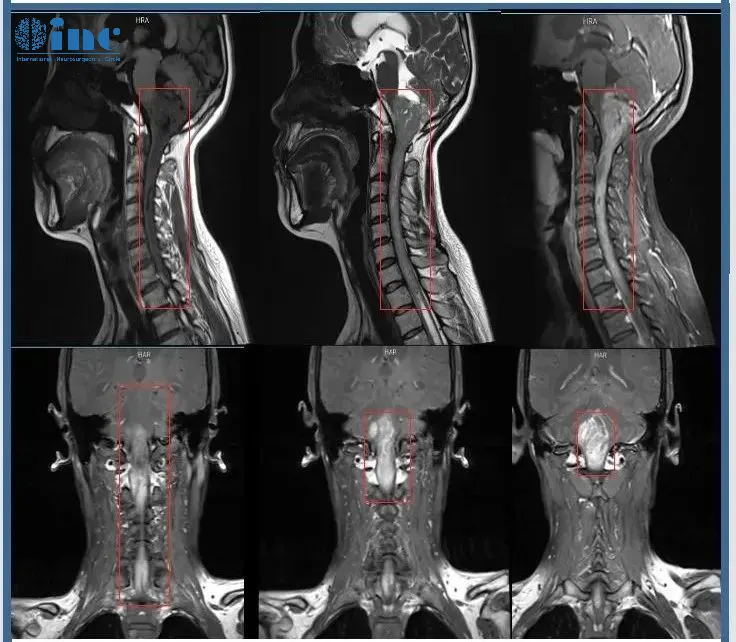

北京時間2022年11月23日,蘇州大學附屬第四醫(yī)院手術室,歷經12個半小時的高難度手術,終于從33歲鄭女士的腦中,成功切除一顆巨大的腦干-脊髓髓內腫瘤!該腫瘤起源于腦干下部,累及延髓和顱頸交界區(qū),且向下方延伸到整個頸部脊髓以及一直到第一胸椎水平,病變累及范圍近15cm,這個位置的手術稍有不慎,患者可能就要面臨癱瘓、呼吸心跳暫停、昏迷植物人等毀滅性的結果。為了更好的保護該名患者的正常神經功能并切除腫瘤,僅僅延髓、脊髓部位的腫瘤剝離就用了4個小時。

術前MR

看著影像片子上這條長度可怕的腫瘤,同為醫(yī)務工作者的鄭女士非常清楚手術的風險,腦干是生命中樞,脊髓是連接大腦與周圍神經系統(tǒng)的主要通路,其中一處長腫瘤,不管腫瘤帶來的威脅還是手術的風險,都是難以想象的,何況自己的這條病變范圍累及15cm的大腫瘤。能安全手術的主刀醫(yī)生也非常少,在查閱了許多專業(yè)的醫(yī)學資料后,鄭女士將目光鎖定在國際腦干手術專家——INC德國巴特朗菲教授身上??粗暧椎暮⒆?,和身邊為自己擔憂的愛人,鄭女士決定尋求他的示范手術……

“影像資料顯示非常廣泛的髓內腫瘤,起源于腦干下部,受累延髓和顱頸交界區(qū)-且向下方延伸到整個頸部脊髓以及一直到第一胸椎水平。我以前成功地做過類似巨大腫瘤患者的手術,但是我必須說明,這種巨大腫瘤的切除術非常費力和耗時,就像兩臺獨立的手術,因為不僅是腫瘤的切除需要時間,而且還要行廣泛的椎板成形術(從頸1到胸1水平)以及枕下開顱術。病人應該在腫瘤比現(xiàn)在小的時候更早接受手術。手術是可行的,也是必要的。”